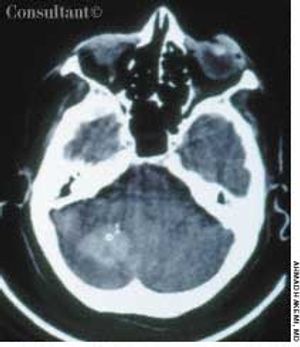

A 65-year-old woman with a long history of hypertension treated with metoprolol and felodipine complained of dizziness, headache, nausea, and vomiting of acute onset. Her blood pressure was 220/110 mm Hg. She was drowsy and unable to stand or walk.